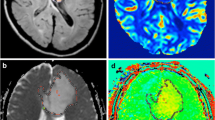

An expert radiologist examined the in-phase and opposed-phase images. Three 20–30-mm2 oval regions of interest (ROIs) were placed manually in the solid component in the in-phase and opposed-phase images, and the average signal intensity (SI) values were determined. The ROI was taken from the same solid area from which the MRS sequence was obtained. The solid part of the tumor is defined as the part of the tumor that is isointense on T1-weighted (T1W) images and presents an iso- to hyperintense signal on T2-weighted (T2W) images. The same “solid component” was used on both SVS and IOP imaging analyses. Based on the presence of the decreased SI area in the opposed-phase sequences by visual evaluation, we found the most suitable location for the ROI. The same ROIs were then used consistently across both sequences (Fig. 2).

A 60-year-old man with high-grade glioma. a Magnetic resonance spectroscopy (MRS) showed elevated choline and low N-acetylaspartate (NAA) levels with lactate peak. b Three regions of interest were placed on each chemical shift sequence (right: opposed-phase, left: in-phase) to calculate the mean signal intensities and corresponding signal loss ratio